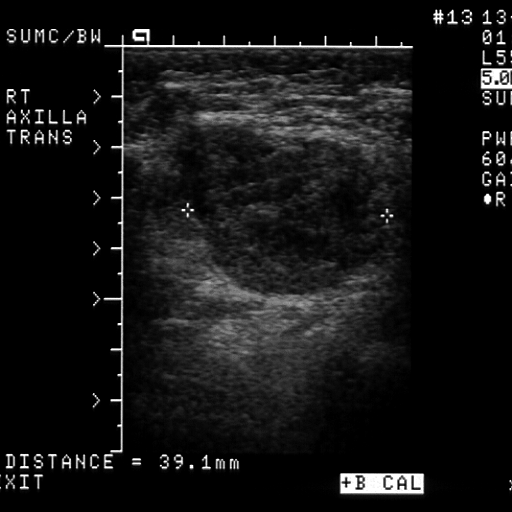

From www.clinicalimaging.org

Cystic metastatic lymph nodes in malignant melanoma a case report Clinical Imaging Melanoma In Lymph Nodes Having a sentinel lymph node biopsy (slnb) can tell whether. learn what the different stages of melanoma mean, from stage 0 to stage 4 metastatic melanoma and what factors doctors use to determine how advanced. Patients with melanomas deeper than 0.8 mm, those who have ulceration under the microscope in. lymph nodes play a big role in the. Melanoma In Lymph Nodes.

Cystic metastatic lymph nodes in malignant melanoma a case report Clinical Imaging Melanoma In Lymph Nodes Patients with melanomas deeper than 0.8 mm, those who have ulceration under the microscope in. lymph nodes play a big role in the body and in cancer care. for melanoma, targeted therapy might be recommended if the cancer has spread to your lymph nodes or to. Having a sentinel lymph node biopsy (slnb) can tell whether. when. Melanoma In Lymph Nodes.

Cystic metastatic lymph nodes in malignant melanoma a case report Clinical Imaging Melanoma In Lymph Nodes Having a sentinel lymph node biopsy (slnb) can tell whether. Patients with melanomas deeper than 0.8 mm, those who have ulceration under the microscope in. for melanoma, targeted therapy might be recommended if the cancer has spread to your lymph nodes or to. Common sites for metastases include the. learn how melanoma can spread through the lymphatic system. Melanoma In Lymph Nodes.